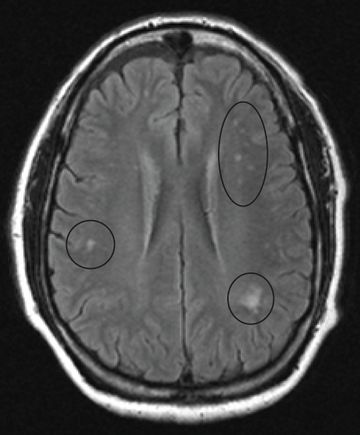

في الدماغ نفسها، التغييرات أقل حدة: تحدث عندما تتحلل مصادر صغيرة من الألياف العصبية وتراكم الخلايا النجمية، وعادة ما تكون تحت القشرة، وكذلك نزيف دائري مع طارة من الخلايا الدبقية.

قد يُظهر التصوير بالرنين المغناطيسي للدماغ تشوهات في المادة البيضاء حول البطينات. قد يُظهر التصوير بالرنين المغناطيسي للحبل الشوكي كثافة في الشدة الخطية في الجزء الخلفي من المسالك العنقية للحبل الشوكي، مع مشاركة انتقائية للأعمدة الخلفية.